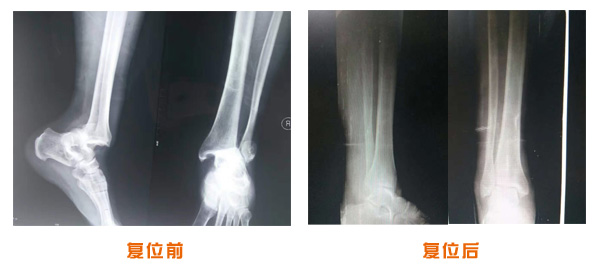

肥城市安駕莊梁氏骨科醫(yī)院是一所以梁氏手法正骨配合膏藥為特色的現(xiàn)代化專科醫(yī)院。

梁氏骨科術(shù)始創(chuàng)于清雍正年間,歷經(jīng)八代,至今已有三百年歷史。據(jù)1929年泰安縣志載“梁瑞圖先生,字增生,號(hào)蓮峰,安駕莊人,精岐黃并發(fā)明接骨,凡跌打車凡跌打車軋皮不破而碎骨者......【詳細(xì)】 |